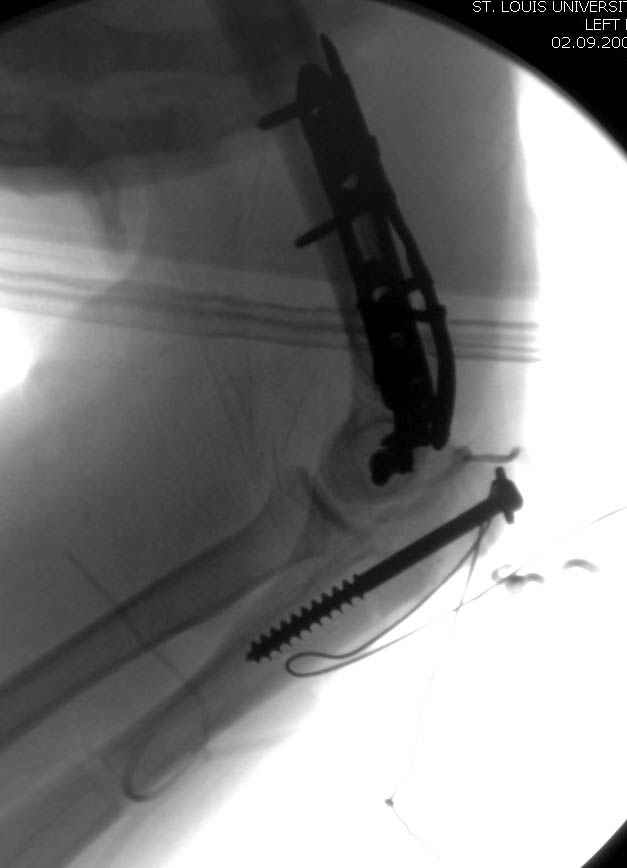

Примерный случай, только перелом был открытый, в задне-медиальной стороне рана около 2 см по характеру "изнутри кнаружи", неврологический статус со слабостью сгибания мизинца, также слабая абдукция и аддукция указательного пальца и сгибания в кисти.

Больному сделали обработку и наложили временный аппарат внешной фиксации плечо-предплечье.

На шестой день сделали открытую репозицию чрезлоктевым доступом двумя locking plate, локтевой нерв был ушибленным, после операции положительная динамика в Flexor Carpi Ulnaris. Фиксацию локтевого отростка произвели tension band technique с дополнительным шурупом.

Этапы операции на снимках....

Джолдас Кульджанов

Djoldas Kuldjanov, MD

Department of Orthopedic Surgery

St. Louis University Medical Center